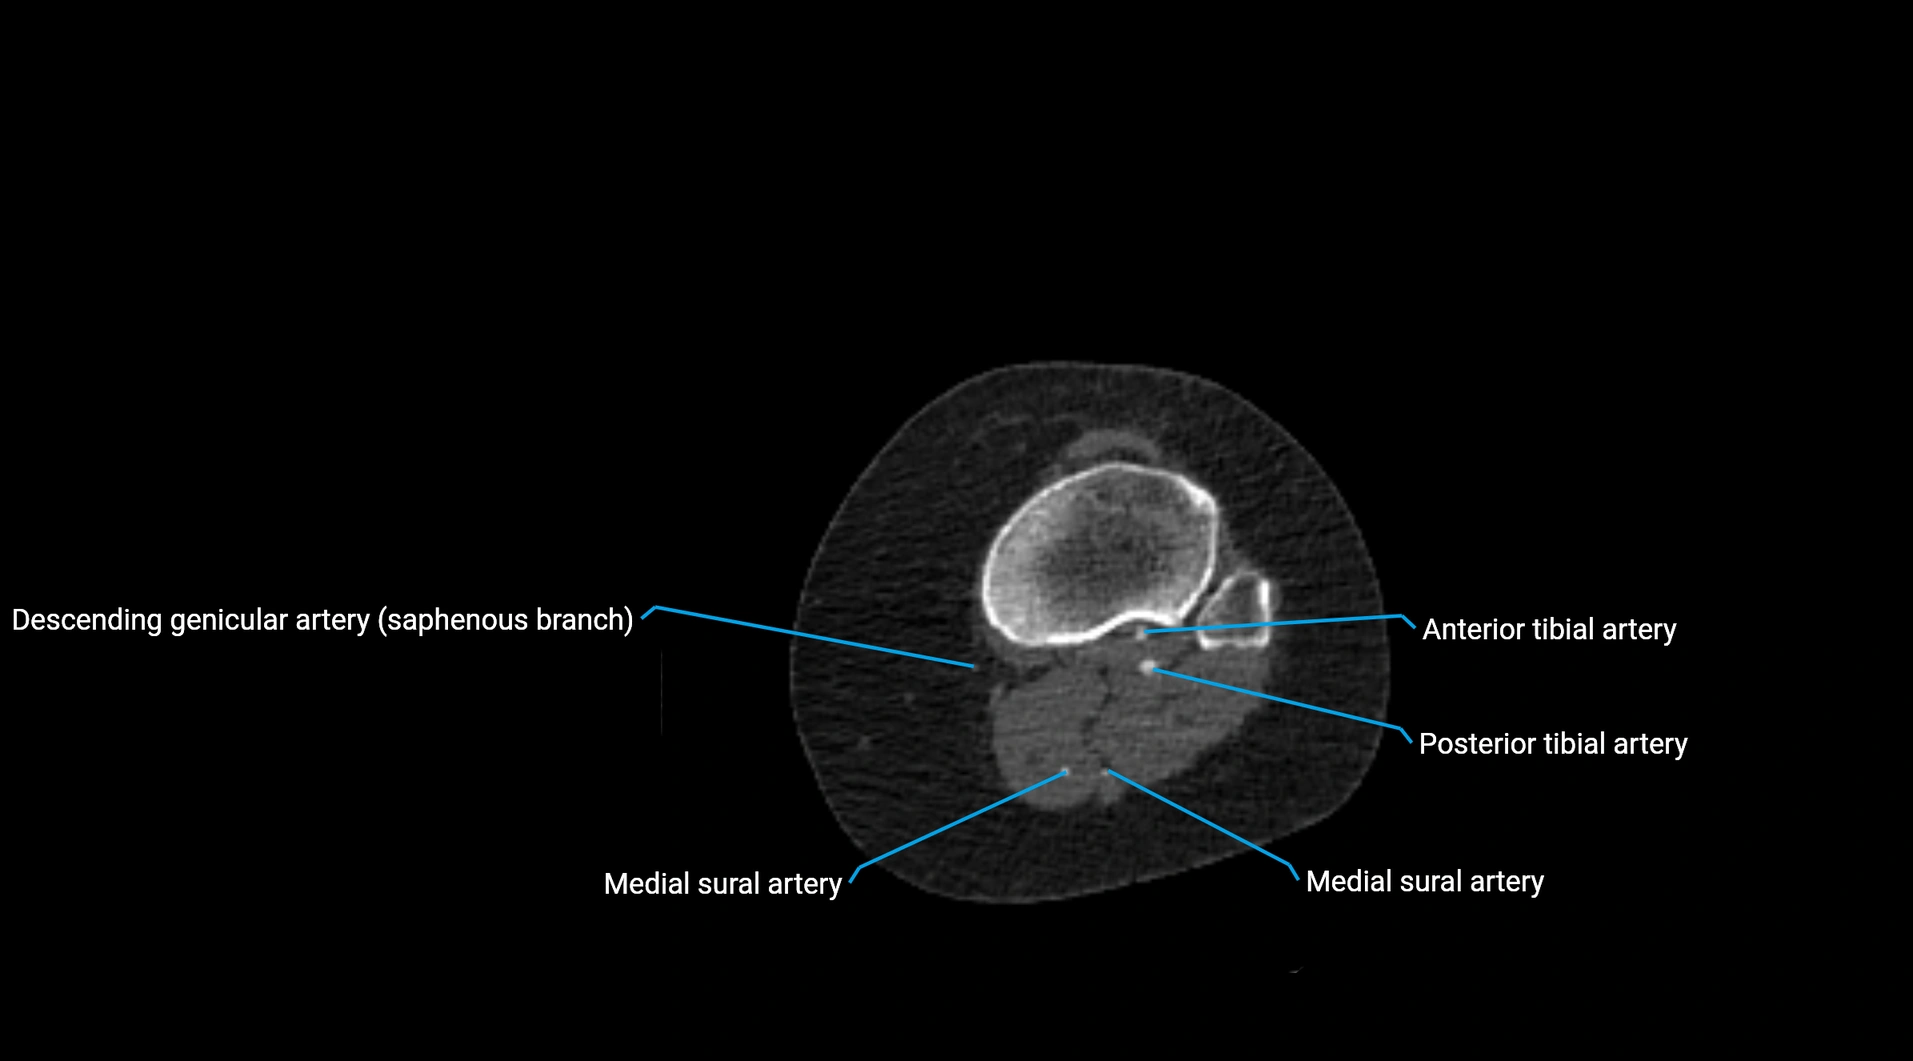

CT images

image

Contrast-enhanced CT (CTA):

• Gold standard for abdominal aortic imaging

• Provides excellent detail of lumen, wall, aneurysm, thrombus, and branch vessels

• Multiplanar and 3D reconstructions help in aneurysm measurement, stent graft planning, and dissection evaluation

• Detects acute rupture, traumatic injury, or occlusion with high sensitivity